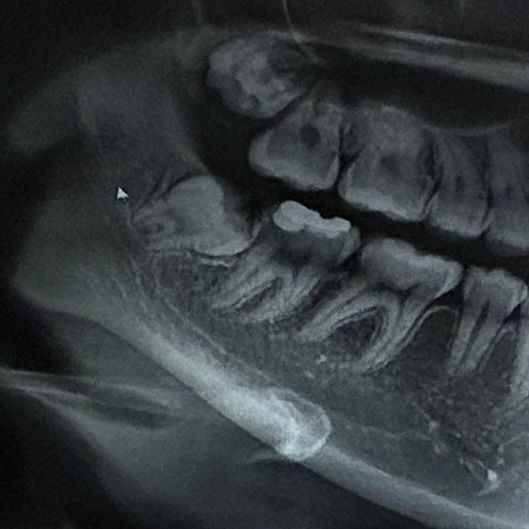

엑스레이가 어두워서 잘 보이진 않지만, 사랑니 영향도 잇지만, 사랑니 앞 치아의 뒤쪽에 충치가 많이 생긴거 같습니다.

현재 사랑니가 앞의 어금니를 밀어내고 있어 이로 인해 통증이 느껴지게 되는 것입니다. 이를 방치시에 어금니가 상하게 되기에 빠른시일내에 사랑니발치를 하길 권합니다.